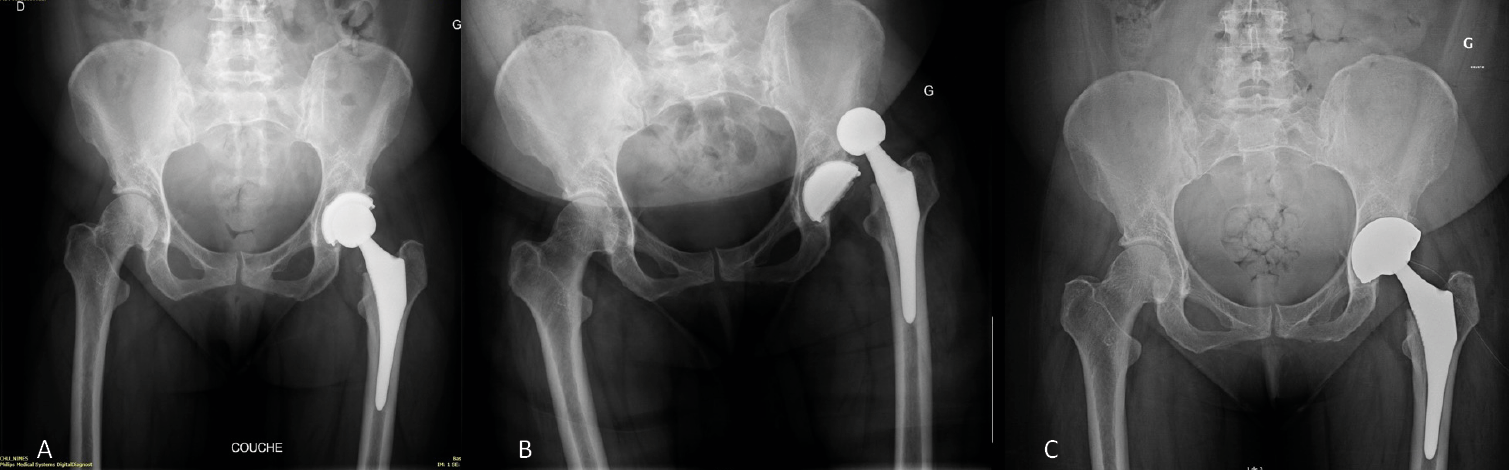

Acetabular and femoral revisions in THA